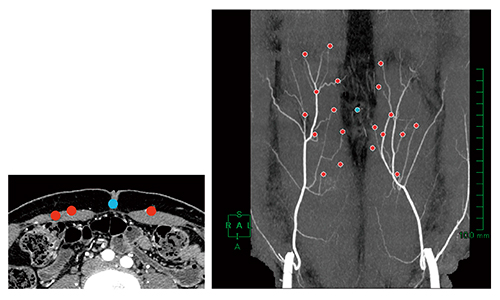

図4 両下腹壁動脈MIP画像

細血管解析で穿通枝の抽出が終了した後,3Dレイヤーに移動し,腹壁のマスクを作成する。腹壁と穿通枝をマルチレイヤー表示させれば完成である。

図5 マーキングした両下腹壁動脈MIP画像

形成外科医とともに臍(●)と筋膜からの分岐箇所(●)にマークを描画し,術前画像の完成である。